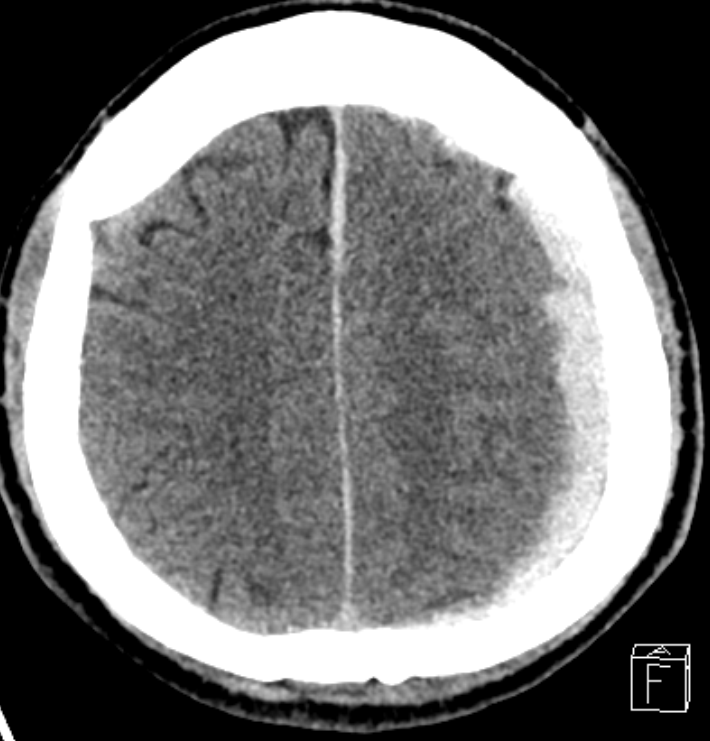

1.세포독성 뇌부종은 혈액-뇌-장벽(BBB)은 비교적 유지된 상태에서 발생하는 부종으로, 뇌세포 자체의 대사 장애로 인해 수분이 세포 내로 이동하면서 발생하는 부종임. 2.혈관성 부종처럼 혈관 밖이 아니라 세포 안에 수분이 축적되는 것이 특징임. 3.주된 원인은 뇌경색, 저산소증, 저혈당, 독성 손상 등으로 세포의 에너지 대사 장애가 발생하면서 Na⁺/K⁺-ATPase 펌프 기능이 저하됨. 4. Na⁺/K⁺-ATPase 펌프는 나트륨은 세포 밖으로 내보내고, 칼륨은 세포 안으로 들어보내는 역할은 하여, 세포 안의 물이 적절하게 유지되고 세포 정상 크기를 유지함 5.에너지 고갈로 인해 능동적 이온 운반이 실패하면서, 세포막을 통한 이온 항상성이 붕괴됨. 6. Na⁺/K⁺-ATPase기능 저하로 인해 세포 ..

공부 요약 2026.02.05